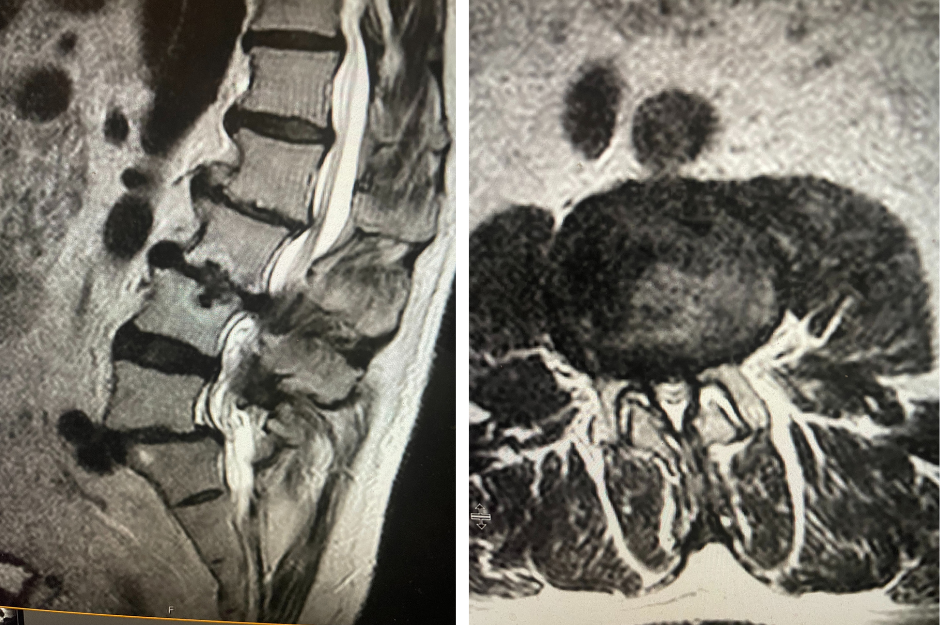

Figure 2. T2-weighted sagittal and axial MRIs demonstrating severe L3-4 stenosis and an L5-S1 grade 1 spondylolisthesis and spondylolysis and L3-4 retrolisthesis. Note the anterior osteophyte formation at L2-3 with attempted autostabilization of segment.

He had mild proximal weakness of his hip flexors.  He also had a history of diabetes, hypertension, and hypercholesterolemia. Imaging studies were obtained. Plain x-rays (Fig. 1) demonstrated a degenerative levoscoliosis with the apex of the curve at L2-3. Lumbar MRI (Fig. 2) showed severe degenerative disc disease with an L5-S1 grade 1 spondylolisthesis and a significant retrolisthesis at L3-4 with severe lumbar stenosis.